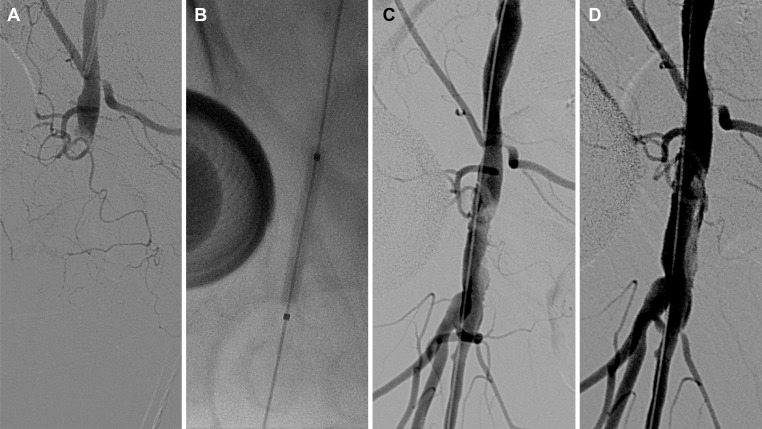

Fig 4. A 70-year-old woman developed acute ischemia of the right leg after percutaneous coronary intervention.

(a) Total occlusion of the common femoral artery was revealed with angiography using a contralateral femoral approach. (b, c) Prolonged inflation of an angioplasty balloon was performed. (d) After completion, angiography revealed revascularization of the common femoral artery with a non-flow-limiting intimal dissection. The superficial and deep femoral arteries demonstrated patency, and stenting was not necessary.